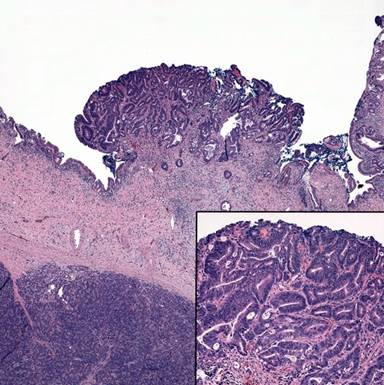

The final surgical pathology report revealed two discrete tumors associated with dysplasia. As seen in the endoscopic ampullectomy, a 1.5 cm invasive moderately differentiated intestinal type ampullary adenocarcinoma was identified associated with a periampullary/duodenal adenoma with high grade dysplasia (Figure 4). The tumor was located at the junction of the ampulla and the duodenal mucosa, at the papilla. The second tumor was described as a 0.4 cm raised polypoid lesion located 1.5 cm away from the ampullary tumor, arising in the distal (intrapancreatic) common bile duct. It was classified as a moderately differentiated biliary adenocarcinoma associated with low and high grade dysplasia of the surrounding biliary epithelium (Figure 5). All resection margins, including the common bile duct, pancreatic and retroperitoneal margins were negative for dysplasia and invasive carcinoma. Twenty-eight lymph nodes were examined, and all were negative for metastatic adenocarcinoma. The pancreas showed chronic pancreatitis and rare foci of Pan-In 1 and 2. The case was reviewed by a second gastrointestinal pathologist who concurred with the diagnosis. The final pathologic stage for both tumors was stage I (T1N0M0). The patient was presented at University of Colorado Gastro-Intestinal Tumor Board and given the early stage of both malignancies and the patient’s age, close observation was recommended.

Figure 4. Histology revealed low and high grade dysplasia of the peri-ampullary intestinal epithelium associated with an invasive adenocarcinoma composed of large well-formed glands. |